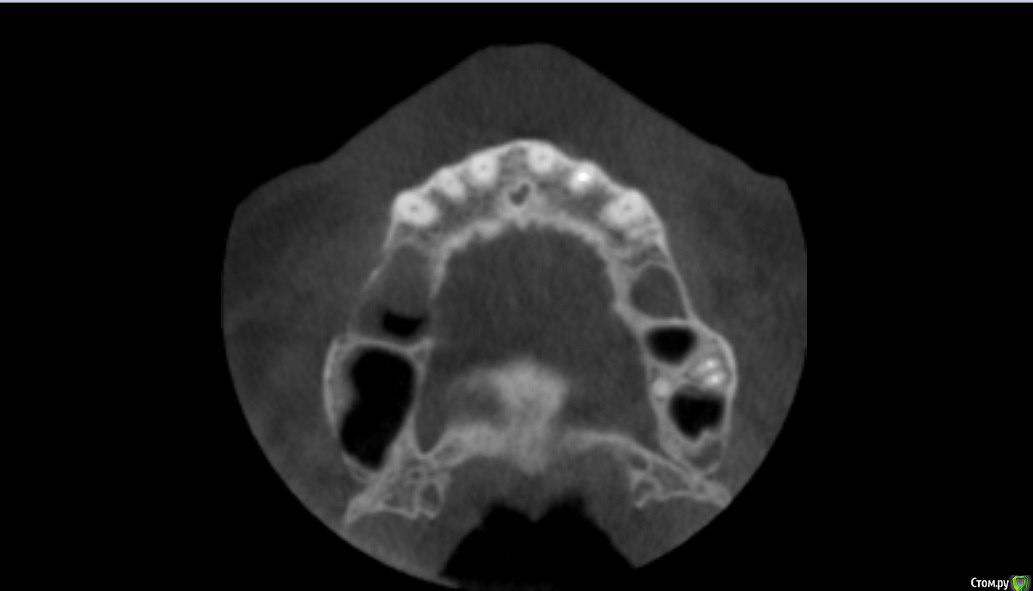

Kovalov Igor Опубликовано 19 мая, 2016 Поделиться Опубликовано 19 мая, 2016 (изменено) Здравствуйте уважаемые форумчане! Нужен совет по повторному синуслифтингу....3 месяца назад проводилась попытка синуслифтинга в 1 сегменте, отсутствие 14,15,16 зубов ... Разрез, формирование окна, в этом случае выбрал вход в синус с двух окон в проекции 14 и 16, получить перфу возле септы в области 16 когда отслаивал ... 14 отслойка без проблем... закрыл окна мембраной и ушил отправил погулять на 2,5-3 месяца.Вопрос как поступить ? Сделать одно большое окно? Как быть со спайками и как сложно их отделять ? Мембрану под перфу не подложил так как не делал ниразу этого... Кт после 3х месяцев ... Изменено 19 мая, 2016 пользователем Kovalov Igor Ссылка на комментарий

kriokov Опубликовано 19 мая, 2016 Поделиться Опубликовано 19 мая, 2016 пошел бы стандартно одним окном, да и первый раз думаю надо было одним окном идти, там не полная септа.Иногда приходиться остро работать на спайках как при расщеплении. Не знаю, но мне здесь одно здоровое окно видиться. И наверное зря Вы септу не спилили или не выкусили при первом заходе, если решили через три мес на повторный идти. Синус не плохо выглядит, думаю нормально все будет. 6 Ссылка на комментарий

red_butler Опубликовано 21 мая, 2016 Поделиться Опубликовано 21 мая, 2016 Куда вы 2гр L сыпите та? Тромбуете штоль?Даже еще раз пересмотрел срезы, Вы считаете что на такой операционной площади и при таком строении синуса расход будет меньше? 3 Ссылка на комментарий

Kovalov Igor Опубликовано 21 мая, 2016 Автор Поделиться Опубликовано 21 мая, 2016 Даже еще раз пересмотрел срезы, Вы считаете что на такой операционной площади и при таком строении синуса расход будет меньше?Ушло 2 грамма вы правы! ))) Спасибо всем за советы , ошибки были в первом случае малое и высоко расположенное окно, сделал в этот раз одно большое окно, спайки были только по периметру окна , было ощущение что окно начало заростать костью через три месяца, будто пластинка была поверх мембраны , может показалось ...Отслаивал до септы, графт 1,5 гр. в синус и 0,5 латерально от винтов и укрыл мембраной 25*25 владмива, мембрана не понравилась если честно ) Ссылка на комментарий